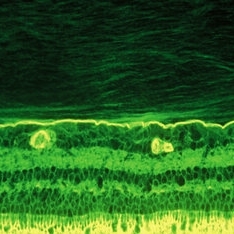

Immunohistochemistry of a monkey eye imaged with fluorescein conjugated ABA lectin staining demonstrates the lamellar structure pf the posterior vitreous cortex. During anomalous PVD, there can be splitting between these lamellae, a phenomenon known as vitreoschisis. (original magnification = 400x)

Condition/keywords: vitreous